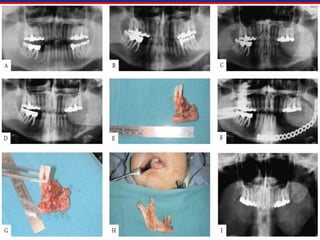

33..Removal of the source ofRemoval of the source of

infectioninfection

 Ultimate goal of treatment is directed at removing theUltimate goal of treatment is directed at removing the

source of infection.source of infection.

 For odontogenic infections, this means endodonticFor odontogenic infections, this means endodontic

treatment, or extraction of the offending dentition.treatment, or extraction of the offending dentition.

 Should be done concurrently with establishment ofShould be done concurrently with establishment of

drainage of the involved space (s).drainage of the involved space (s).

 Antimicrobial aids in eliminating infections from the body.Antimicrobial aids in eliminating infections from the body.

But are not curative so long as the source of infection isBut are not curative so long as the source of infection is

present.present.

 In OMFS, treatment is incision and drainage (I&D) of theIn OMFS, treatment is incision and drainage (I&D) of the

involved space and removal of the causative agent.involved space and removal of the causative agent.

Removal of the causeRemoval of the cause

44..Surgical treatmentSurgical treatment

 Sterile preparation and draping.Sterile preparation and draping.

 Aspiration of the swelling for investigation &Aspiration of the swelling for investigation &

samplingsampling

 Place 1-2 cm incision in a healthy skin orPlace 1-2 cm incision in a healthy skin or

mucosa not over most fluctuant areamucosa not over most fluctuant area

 Place skin incision in aesthetically acceptablePlace skin incision in aesthetically acceptable

area.area.

 blunt dissection with instrument and/or finger.blunt dissection with instrument and/or finger.

 Use shortest and most direct route to theUse shortest and most direct route to the

space.space.

 Secure drains, penrose or red rubberSecure drains, penrose or red rubber

catheters, avoid gauze drainscatheters, avoid gauze drains

Surgical drainage and incisionSurgical drainage and incision